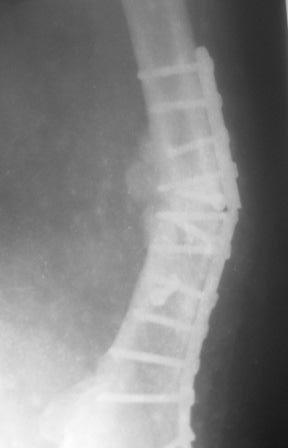

Обратился больной 54г. Травму получил в ноябре 2007г. Оперирован в Алмате (Казахстан). Через 2 мес. гипс снят, потом еще гипс на 2 месяц, с тех пор ходит двумя костылями, последние время беспокоит усиливающаяся боль и деформация.

Локально: укорочение ноги на 3,5см, умеренная отечность и вальгусная деформация, умеренная болезненность, патологической подвижности почти не определяется, но имеется наружная ротация конечности на 15гр.

Наш план БИОС, но так как при удалении пластини зона ложного сустава открывается, для уверенности производить костную пластику (аутографт или хотя-бы по Хахутову) ??, еще как устранить ротацию?